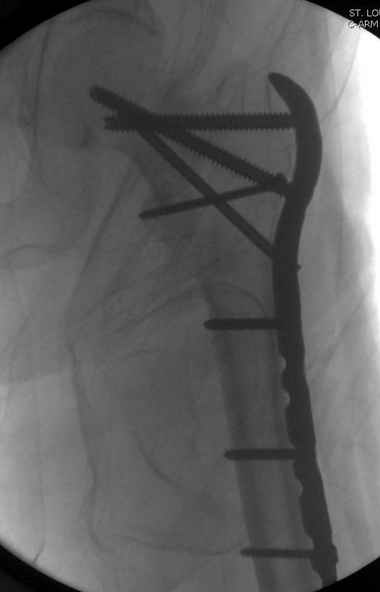

Применили проксимальную Synthes Locking plate, из-за множественных фрагментов посчитали более приемлемым в этом случае (клиника университетская, резиденты должны имет возможность созерцать разные варианты остеосинтеза).

Также старался минимизировать доступ на уровне перелома с субвастус доступом, диафиз фиксирован перкутанно, не стали гонятся за малым вертелом, как смог зафиксировал.